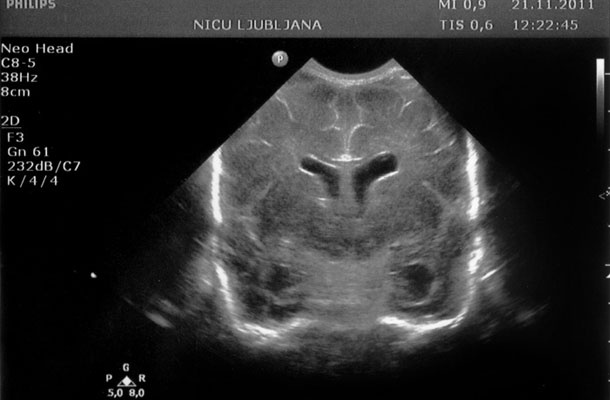

Ultrazvočna slika nezrelih možganov nedonošenčka

Ivana Djilas je pisala o tem, zakaj se za odtroke odločamo s seznamom za in proti. Njen zapis nosi naslov Projekt otrok in je te dni zopet zakrožil po spletu. "Ko se otrok rodi, so njegovi možgani precej nezreli in gladki. Če so nepoškodovani, se bodo na mestih, predvidenih za to, za vsak gibalni in umski vzorec začele vzpostavljati povezave. Možgani se bodo na površini začeli gubati in ustvarjati vijuge. Pri nedonošenčkih je to še bolj izrazito. Presenečeni bi bili, če bi z ultrazvokom vsak teden pogledali skozi veliko mečavo, odprtino med lobanjskimi kostmi novorojenčka: kar naenkrat bi opazili, da so se pojavile vijuge."